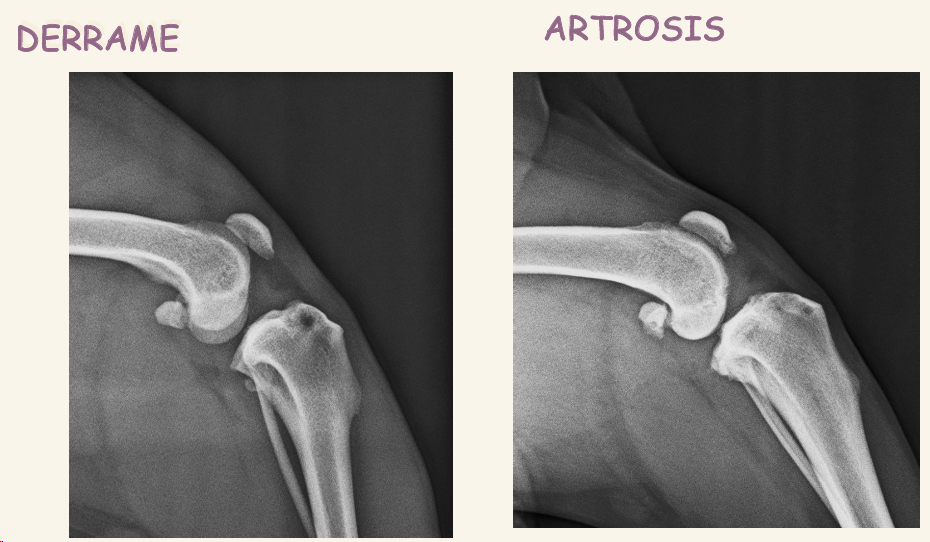

La rotura del ligamento cruzado anterior se ve siempre el desplazamiento de la tibia, patognomonico El primer signo es el derrame, en vez de ver color oscuro vemos zona mas radioopaca, gris

- EDA: Enfermedad Degenerativa Articular

- Rotura del LCA o Ligamento cruzado anterior: TAMBIEN SE VE DERRAME ROTULIANO y desplazamiento de la tibia

Enfermedad degenerativa articular o DEA

- El primer signo radiológico es el derrame, se pierde radiolucidez en tejido entre articulaciones (Disminución de la almohadilla grasa subrotuliana) , se ve gris en vez de negro bajo la rótula

- Otros signos posteriores de artrosis son alteraciones en:

- Osteofitos periartriculares